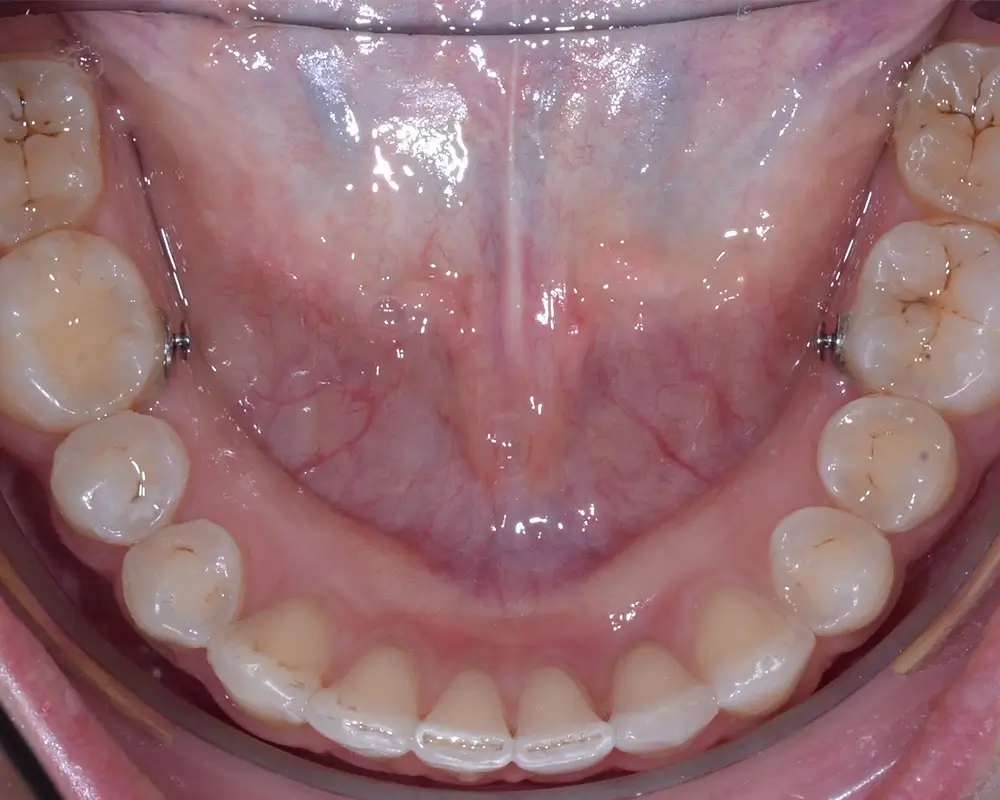

Дистальный прикус - Кейс 4

Эффективность устранения дефекта прикуса посредством элайнеров FlexiLigner.

26

Количество кап НЧ

18

Количество кап ВЧ

Результаты лечения